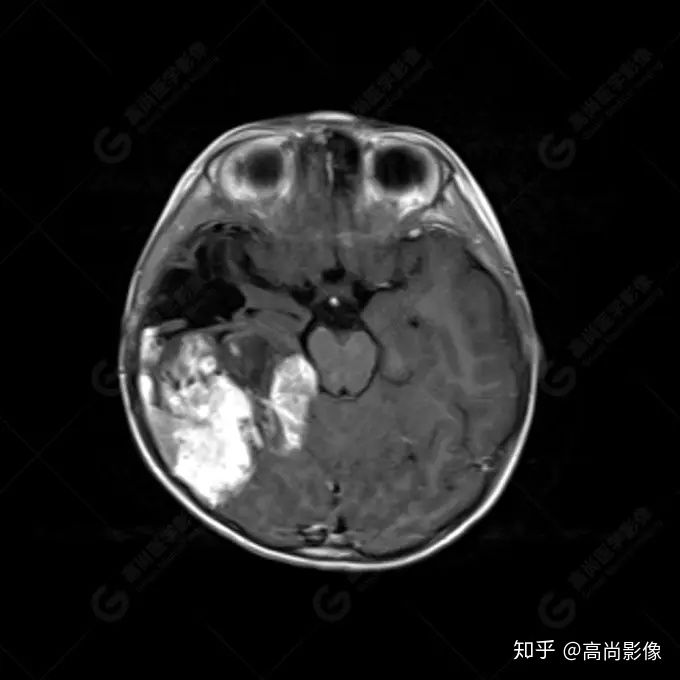

右側(cè)顳葉腫瘤切除術(shù)后(具體不詳):右側(cè)顳部骨質(zhì)不連續(xù)呈術(shù)后改變,右側(cè)顳葉術(shù)區(qū)見片狀長T1長T2信號(hào)影,F(xiàn)LAIR呈低信號(hào);術(shù)區(qū)后方右側(cè)顳枕葉見一巨大占位性病變影,邊界欠清,大小約6.2×5.8×4.3cm(前后×左右×上下),信號(hào)不均勻,T1WI呈等稍低信號(hào)間雜少許高信號(hào),T2WI呈高稍低混雜信號(hào),DWI示部分病灶彌散受限,相應(yīng)ADC圖減低,磁敏感序列見部分呈極低信號(hào),增強(qiáng)掃描可見明顯不均勻強(qiáng)化,鄰近硬腦膜及小腦幕增厚并明顯強(qiáng)化;另延髓右前方及右側(cè)橋小腦角區(qū)見一不規(guī)則形異常信號(hào)影,大小約3.2×1.3×3.7cm(左右×前后×上下),呈長T1稍長T2信號(hào),F(xiàn)LAIR呈等信號(hào),DWI未見受限,增強(qiáng)后明顯均勻強(qiáng)化,鄰近腦膜明顯強(qiáng)化。鄰近腦實(shí)質(zhì)及右側(cè)顳角明顯受壓;左側(cè)大腦半球未見局灶性信號(hào)異常,中線結(jié)構(gòu)稍左移。

右側(cè)顳葉腫瘤切除術(shù)后:現(xiàn)術(shù)區(qū)后方右側(cè)顳枕葉及延髓右前方占位,右側(cè)顳枕部硬腦膜及小腦幕明顯強(qiáng)化,結(jié)合既往影像資料,考慮為胚胎源性惡性腫瘤,如非典型畸胎樣/橫紋肌樣瘤(AT/RT)或原始神經(jīng)外胚層腫瘤(PNET)。